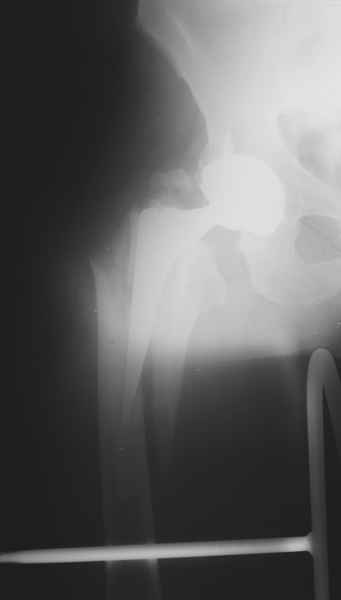

ножка просела немного (вопрос, много - это сколько?)перечисленные проблемы - не самое важное сейчас, на них можно закрыть глаза. Ножка явно нестабильна, проксимальный отломок с б/вертелом к гвоздю не прицепить, срастется ли он с ножкой

1.Остеосинтез на ножке. Мне кажется, что применительно к этому случаю малоперспективный вариант. Синтез хорош, когда можно его выполнить в малоинвазивном исполнении и достигнуть стабильности. Действительно, если ножка б/цементной фиксации после этого не будет иметь фиксации, то ревизия не будет иметь проблем. В представленном случае стабильность синтеза сомнительная, а проведение доп.иммобилизации приведет к контрактуре суставов.

2. Применение ножки дистальной фиксации, мы отдаем предпочтение ножке Вагнера с фиксацией проксимального отдела на ножке. Более травматичное вмешательство, но при стабильной фиксации ножки реабилитация идет в обычном режиме.

Хочется показать два подобных случая, П-ка З. 72 лет и п-т Г. 80 лет. Сразу принимаю замечание, что это были ножки цементной фиксации, просто под руками не было бесцементника.